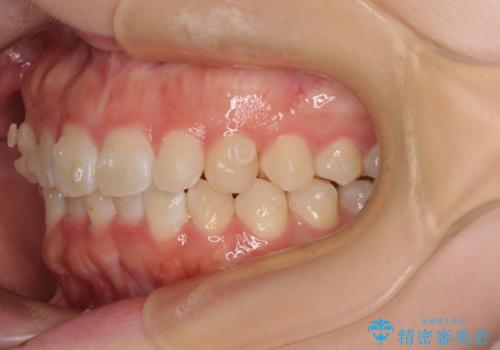

前歯のデコボコを整える インビザラインによる矯正治療

- 上下前歯のデコボコを気にして来院された患者様です。

叢生は軽度であり、ワイヤー矯正でもマウスピース矯正でも対応可能であったので、好きな装置を選んでもらいました。

相談の結果、インビザラインによる矯正治療を行うこととしました。

毎日の装着時間をしっかりと守っていただいたことで、1年程度で無事に治療を終えることができました。